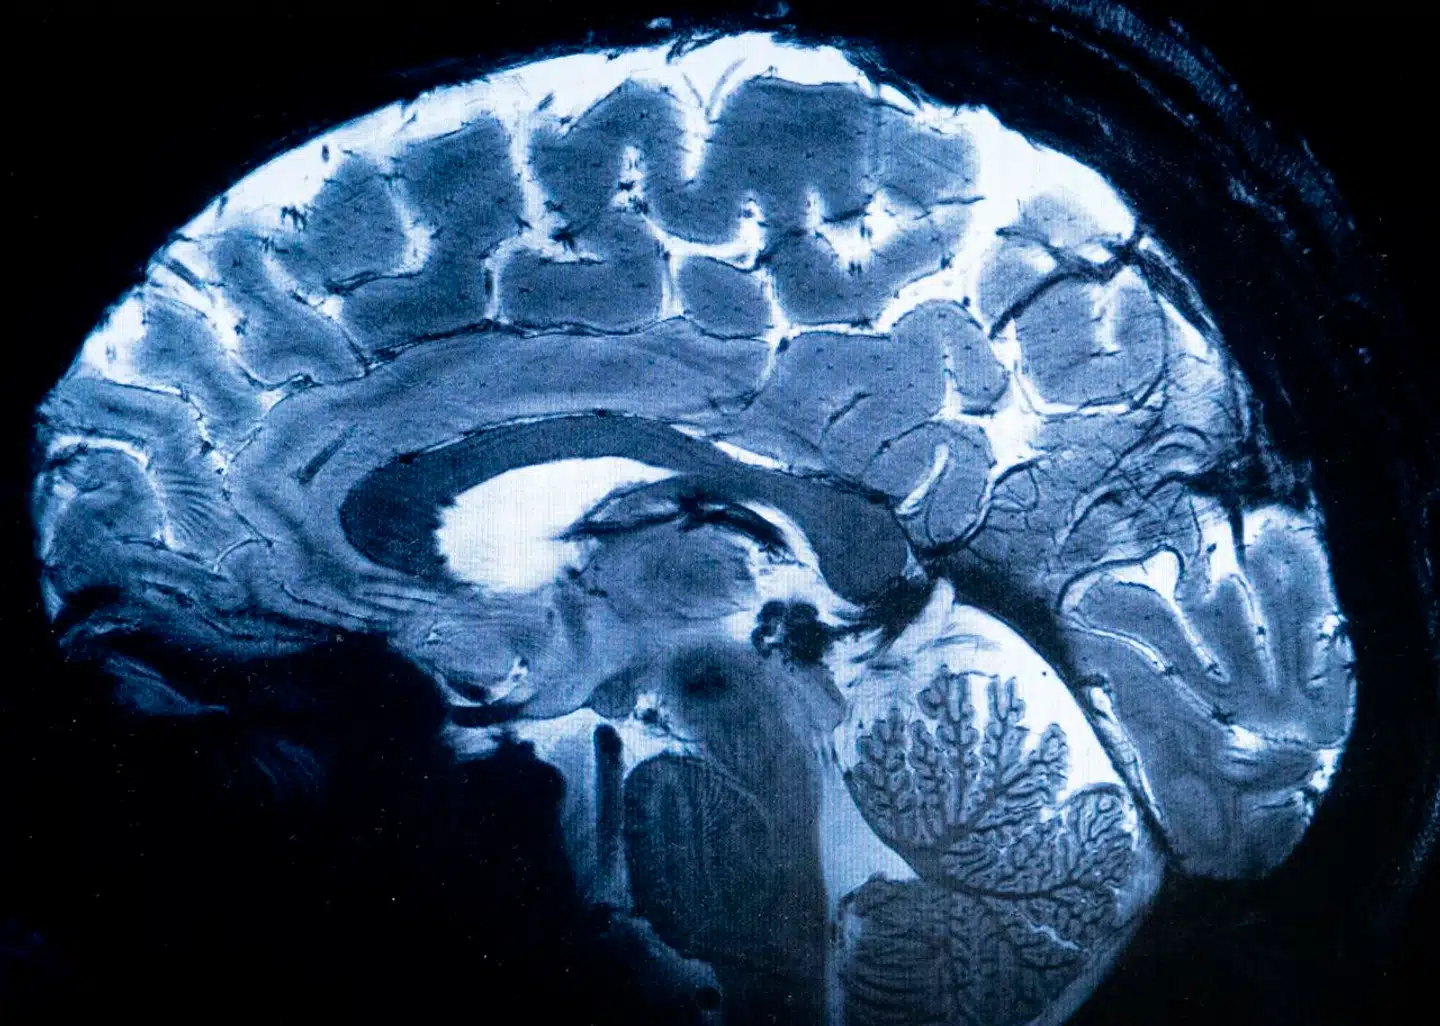

Forskere ved University of Turku i Finland har opdaget, hvor i hjernen stammen opstår. Ved at foretage hjernescanninger på patienter, der er vokset op med lidelsen, og patienter, der er begyndt at stamme efter et slagtilfælde, har forskerne kortlagt, at al stammen skyldes påvirkning af tre hjerneregioner: putamen, der styrer motorik, amygdala, der styrer følelser, og claustrum, der styrer kommunikation. Resultaterne viser, at jo voldsommere de tre hjerneregioner er påvirket, desto mere stammer patienten.